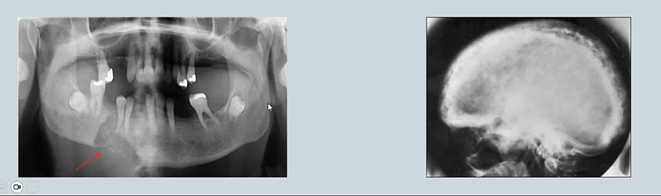

Bone changes as a result of systemic disease

Areas of resorption or patchy resorption and sclerosis in the jaws may be due to skeletal disease and associated with changes in blood chemistry.

Paget's disease →Results in excessive breakdown of bone and dysregulated remodelling.

Bony metastases - mental region in the mandible - radiolucency

Hyperparathyroidism